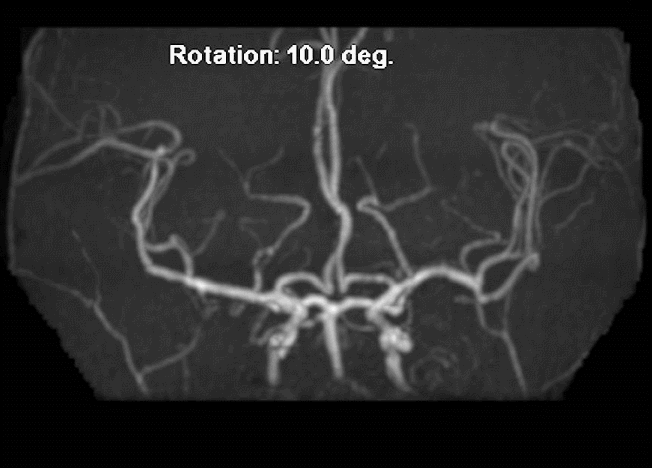

MRI+MRA

脑血管造影(主动脉弓造影及后循环)

右侧颈动脉造影

左侧颈动脉造影

左侧颈内动脉重建(左侧狭窄及扩张较右侧更甚)